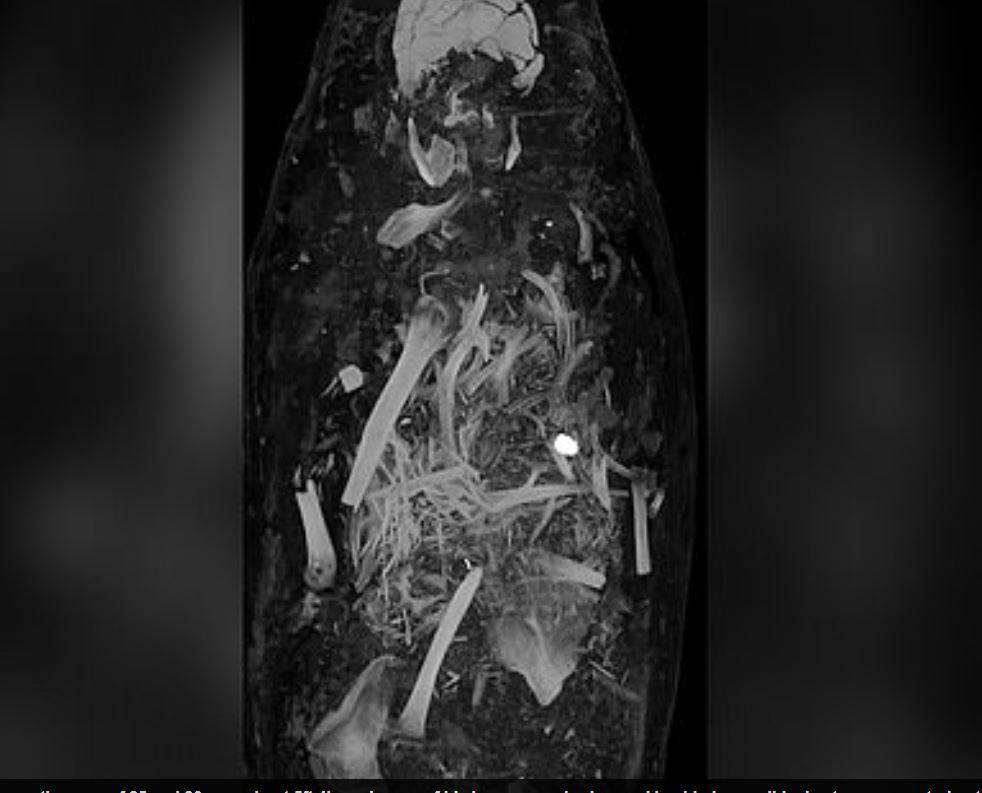

Bilim insanlarının bilgisayarlı tomografi ile incelediği mumyaların tüm organlarıyla birlikte mücevher ve altın sikkelerle gömüldükleri ortaya çıktı.